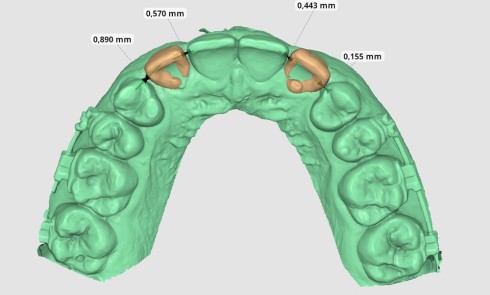

Avec l’essor de la CFAO (Conception et Fabrication Assistées par Ordinateur) et le développement de blocs en composite usinable, il semble intéressant d’en faire usage chez nos jeunes patients. Le but de cet article est de montrer dans quelle mesure la CFAO directe peut s’intégrer au quotidien en odontologie pédiatrique.

Pour cela, dans un premier temps, nous présenterons : le matériel, les indications et le protocole, à l’aide de deux cas cliniques. Dans un second temps, nous récapitulerons les avantages…